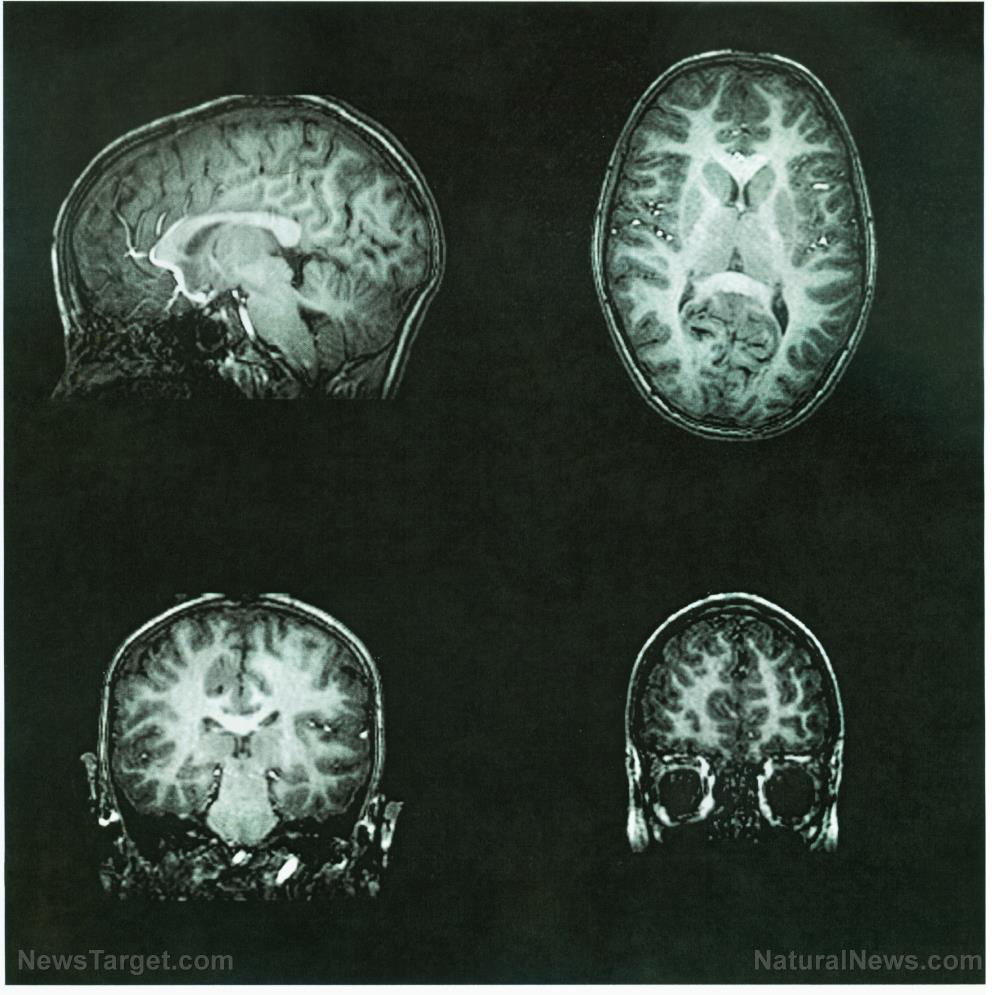

Absolute scientific PROOF that cell phone radiation causes cancer

Most of us are completely dependent on our mobile devices and in total denial about them representing any kind of danger to our health. Unfortunately, the reality is that experts have been warning for some time now that the technology we’ve come to love and depend on – and which, let’s face it, makes our […]